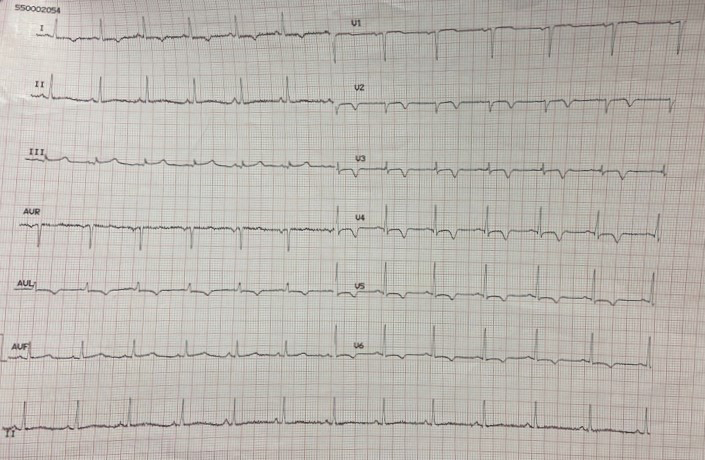

There are two patterns of ECG alteration in Wellens syndrome: type A and type B. Type A, which accounts for 25% of cases, is characterized by biphasic T waves with initial positivity and terminal negativity in leads V2 and V3. Type B, on the other hand, accounts for 75% of cases and is characterized by deeply and symmetrically inverted T waves in leads V2 and V3 (Fig. 1). Despite the differences in the ECG patterns, the progression from type A to type B pattern may occur as a consequence of ischemic damage progression, as proposed by S. W. Smith in his book “The ECG in acute MI” [1].

Fig. 1.

Fig. 1.Electrocardiographic (ECG) changes in Type A (left) and Type B (right) Wellens syndrome.